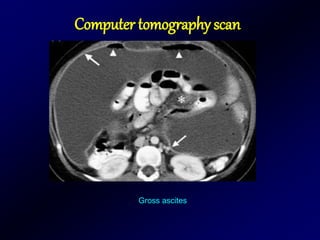

Computer tomography scan

Gross ascites

45

Thickened omentum